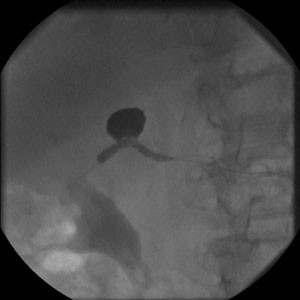

Fig. 1.